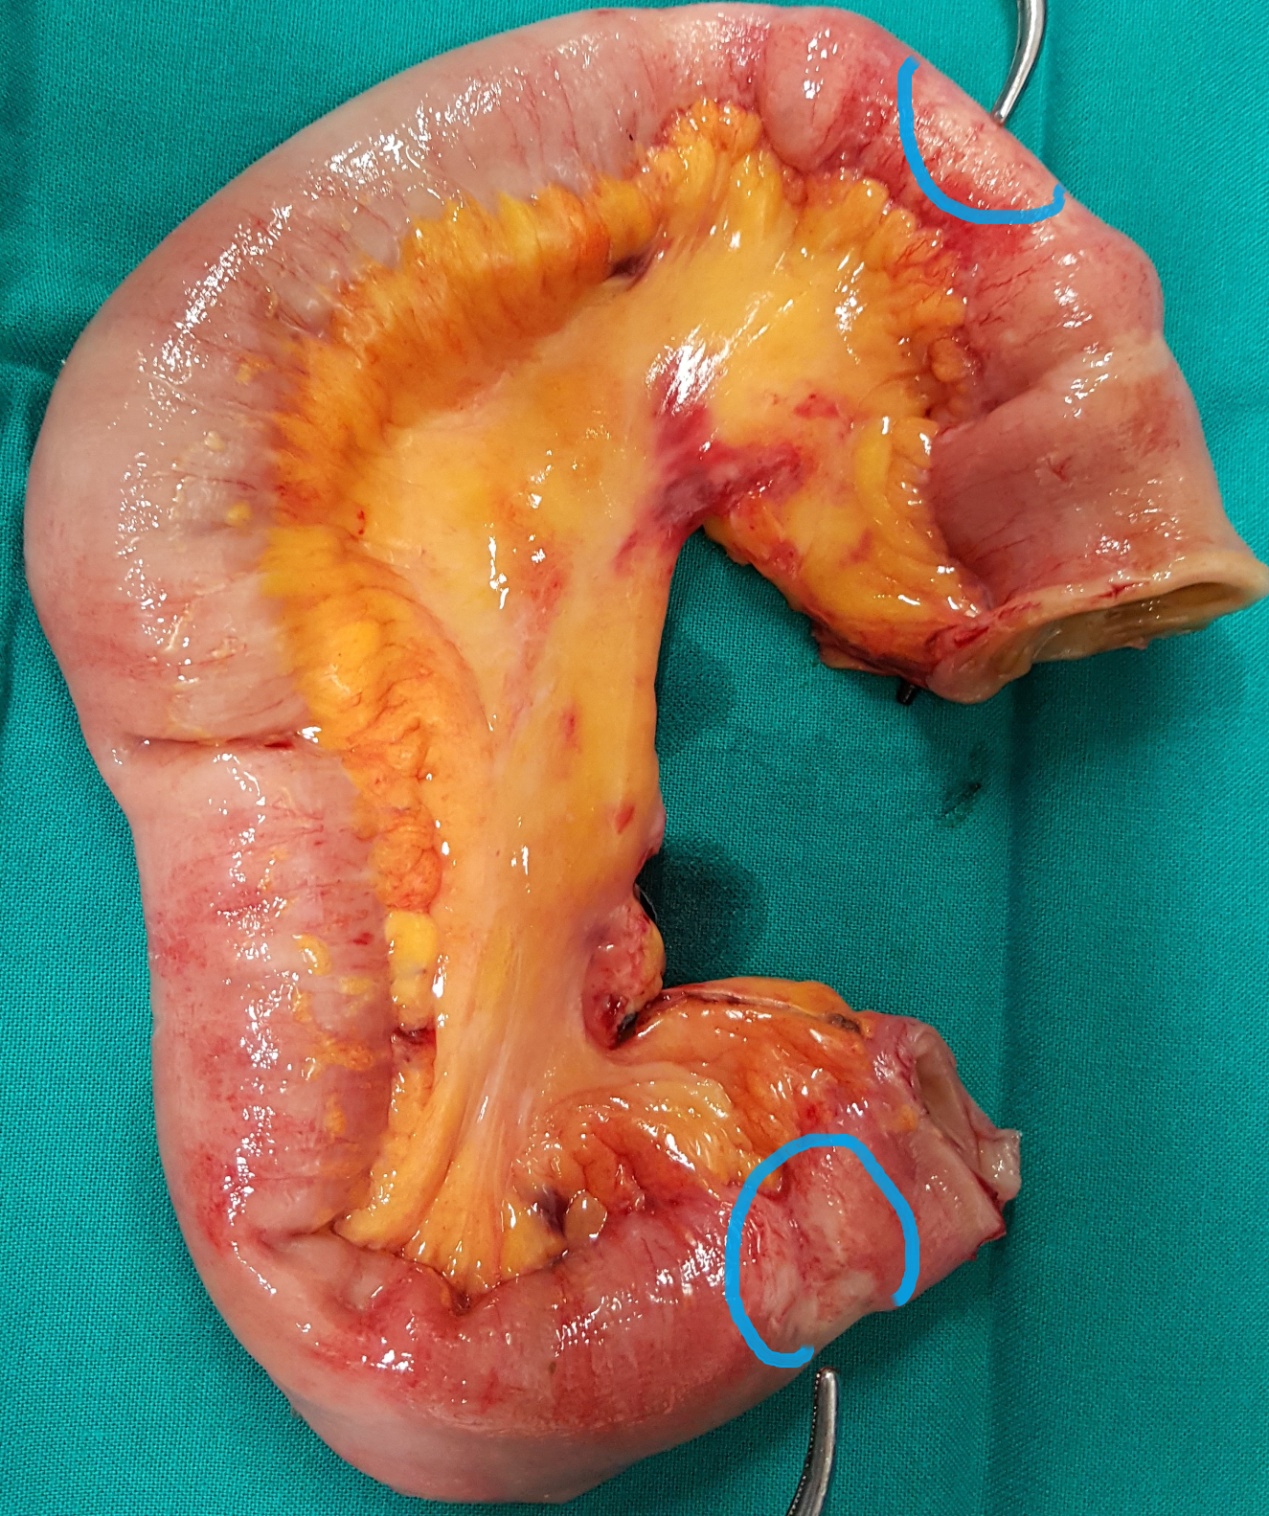

Resected obstructed ileal loop. Blue circles enclose the metastatic foci (Courtesy Dr. V. Penopoulos)

The two metastatic foci causing stenosis and bowel obstruction are clearly visible (Courtesy Dr. V. Penopoulos)